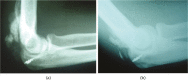

Distal triceps ruptures are rare injuries due to the special anatomical features of the muscle and tendon-bone junction.This injury typically occurs at the tendon-bone junction due to an eccentric contraction of the muscle.The treatment is controversial, especially in partial ruptures; surgical repair is indicated for complete ruptures of the distal triceps tendon.Several repair techniques have been described for acute complete ruptures.Chronic ruptures often require reconstruction rather than direct repair. Cite this article: Demirhan M, Ersen A. Distal triceps ruptures. EFORT Open Rev 2016;1:255-259. DOI: 10.1302/2058-5241.1.000038.